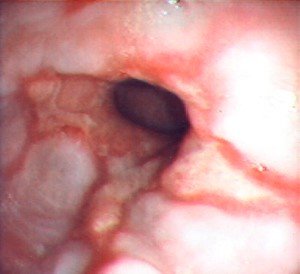

QB-nun orta divertikulu

Həqiqi, traksiyon divertikuldur, QB-nun döş hissəsində, traxeya bifurkasiyasına yaxın bölgədə yerləşir. Kiçik divertikullar adətən əlamətsiz olur, böyük divertikullar isə disfagiya, divertikulit və fistul törədə bilirlər.

Diaqnostikası

Dəqiqləşdirmə

Xəstəliyin dəqiqləşdirilməsi üçün kontrastlı Rentgenoloji müayinə, KT və çox ehtiyatla endskopiya edilməlidir.

- Endoskopiya - divertikulun perforasiyası təhlükəsinə görə çox ehtiyatla aparılmalıdır.